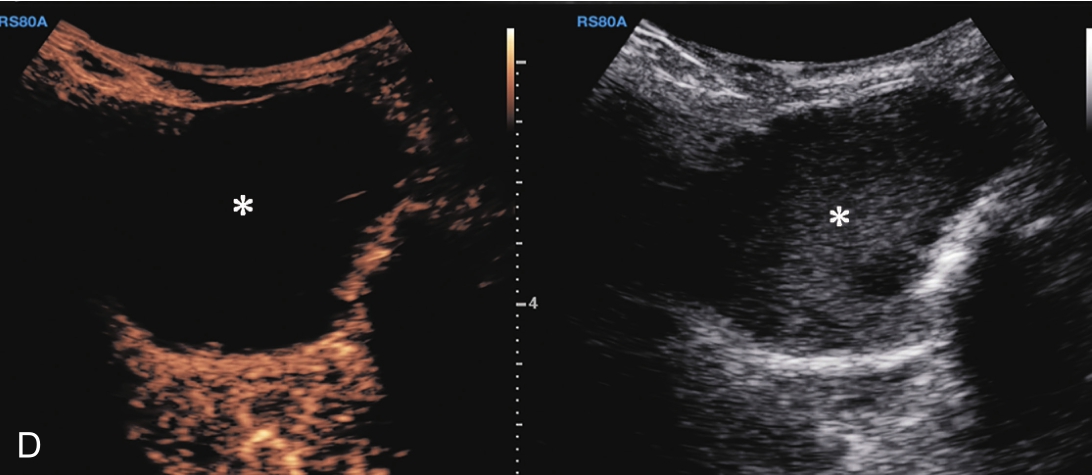

3.当肩袖回声不均匀,有可疑的滑囊面撕裂或全层撕裂,行超声引导下肩峰下-三角肌下滑囊造影检查,可提高对肩袖撕裂的诊断率。方法:将2~5ml生理盐水与0.5ml的超声造影剂混合后,注入肩峰下-三角肌下滑囊,无撕裂的滑囊呈线状高增强(图2-1-8),肩袖滑囊面部分撕裂可见造影剂混合液从滑囊进入肩袖肌腱内而未达肱骨头表面(图2-1-9),若观察到其进入肩关节腔或肱二头肌长头腱鞘,则诊断肩袖全层撕裂(图2-1-10)。

▲ 图2-1-10 超声引导下肩峰下-三角肌下滑囊造影图(三)

A.造影剂从滑囊(单箭头)及冈上肌腱撕裂处达肱骨头表面(双箭头),星号:滑囊撕裂处;B.冈上肌腱(SUP)回声不均匀,箭头:连续的滑囊,星号:滑囊回声中断,HH:肱骨头;C肱二头长头腱鞘内可见造影剂高增强(箭头);D:肱二头肌肌腱横断面(星号),腱鞘内造影剂(箭头);Del:三角肌;LT:肱骨小结节;GT:肱骨大结节

C.彩色多普勒显示囊性团块(星号)内无血流信号;D.超声造影显示囊性团块内呈无增强;E.冈上肌腱完全断裂,关节腔积血(星号);F.超声引导下穿刺液体抽吸及药物注射治疗,箭头示穿刺针